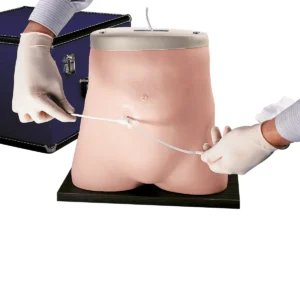

Peritoneal Dialysis Simulator